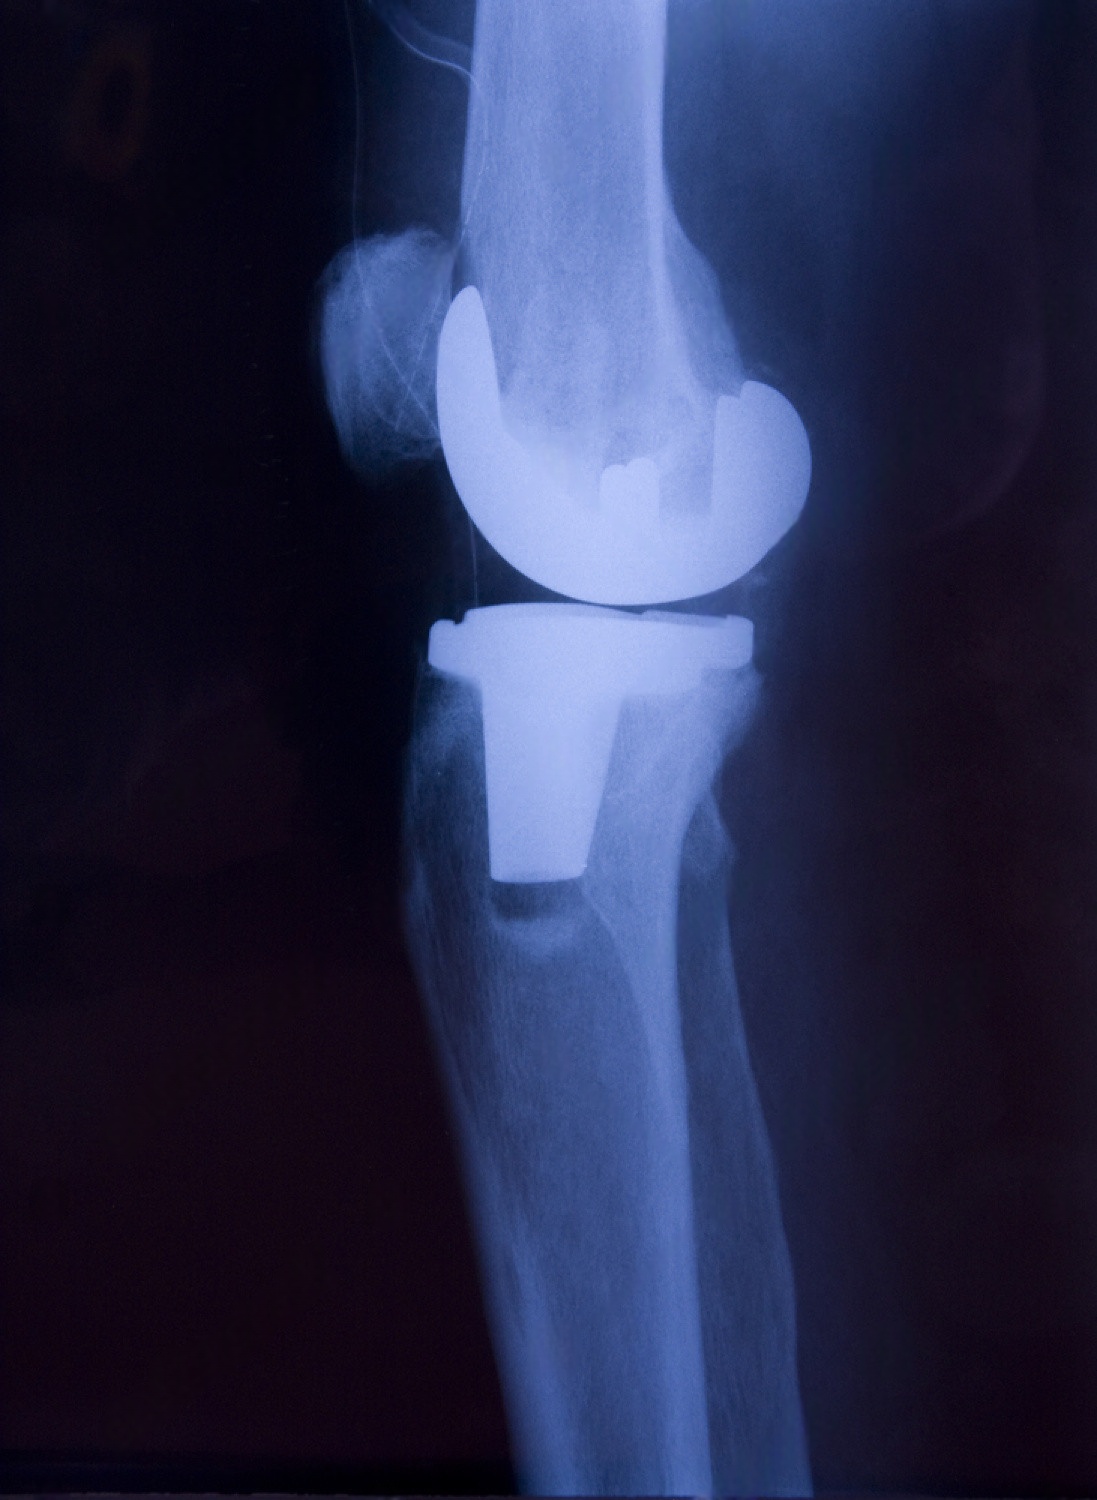

Share your X‑rays, clinical details, and preferred room category to receive a like‑for‑like package quote for knee joint replacement surgery cost in india.